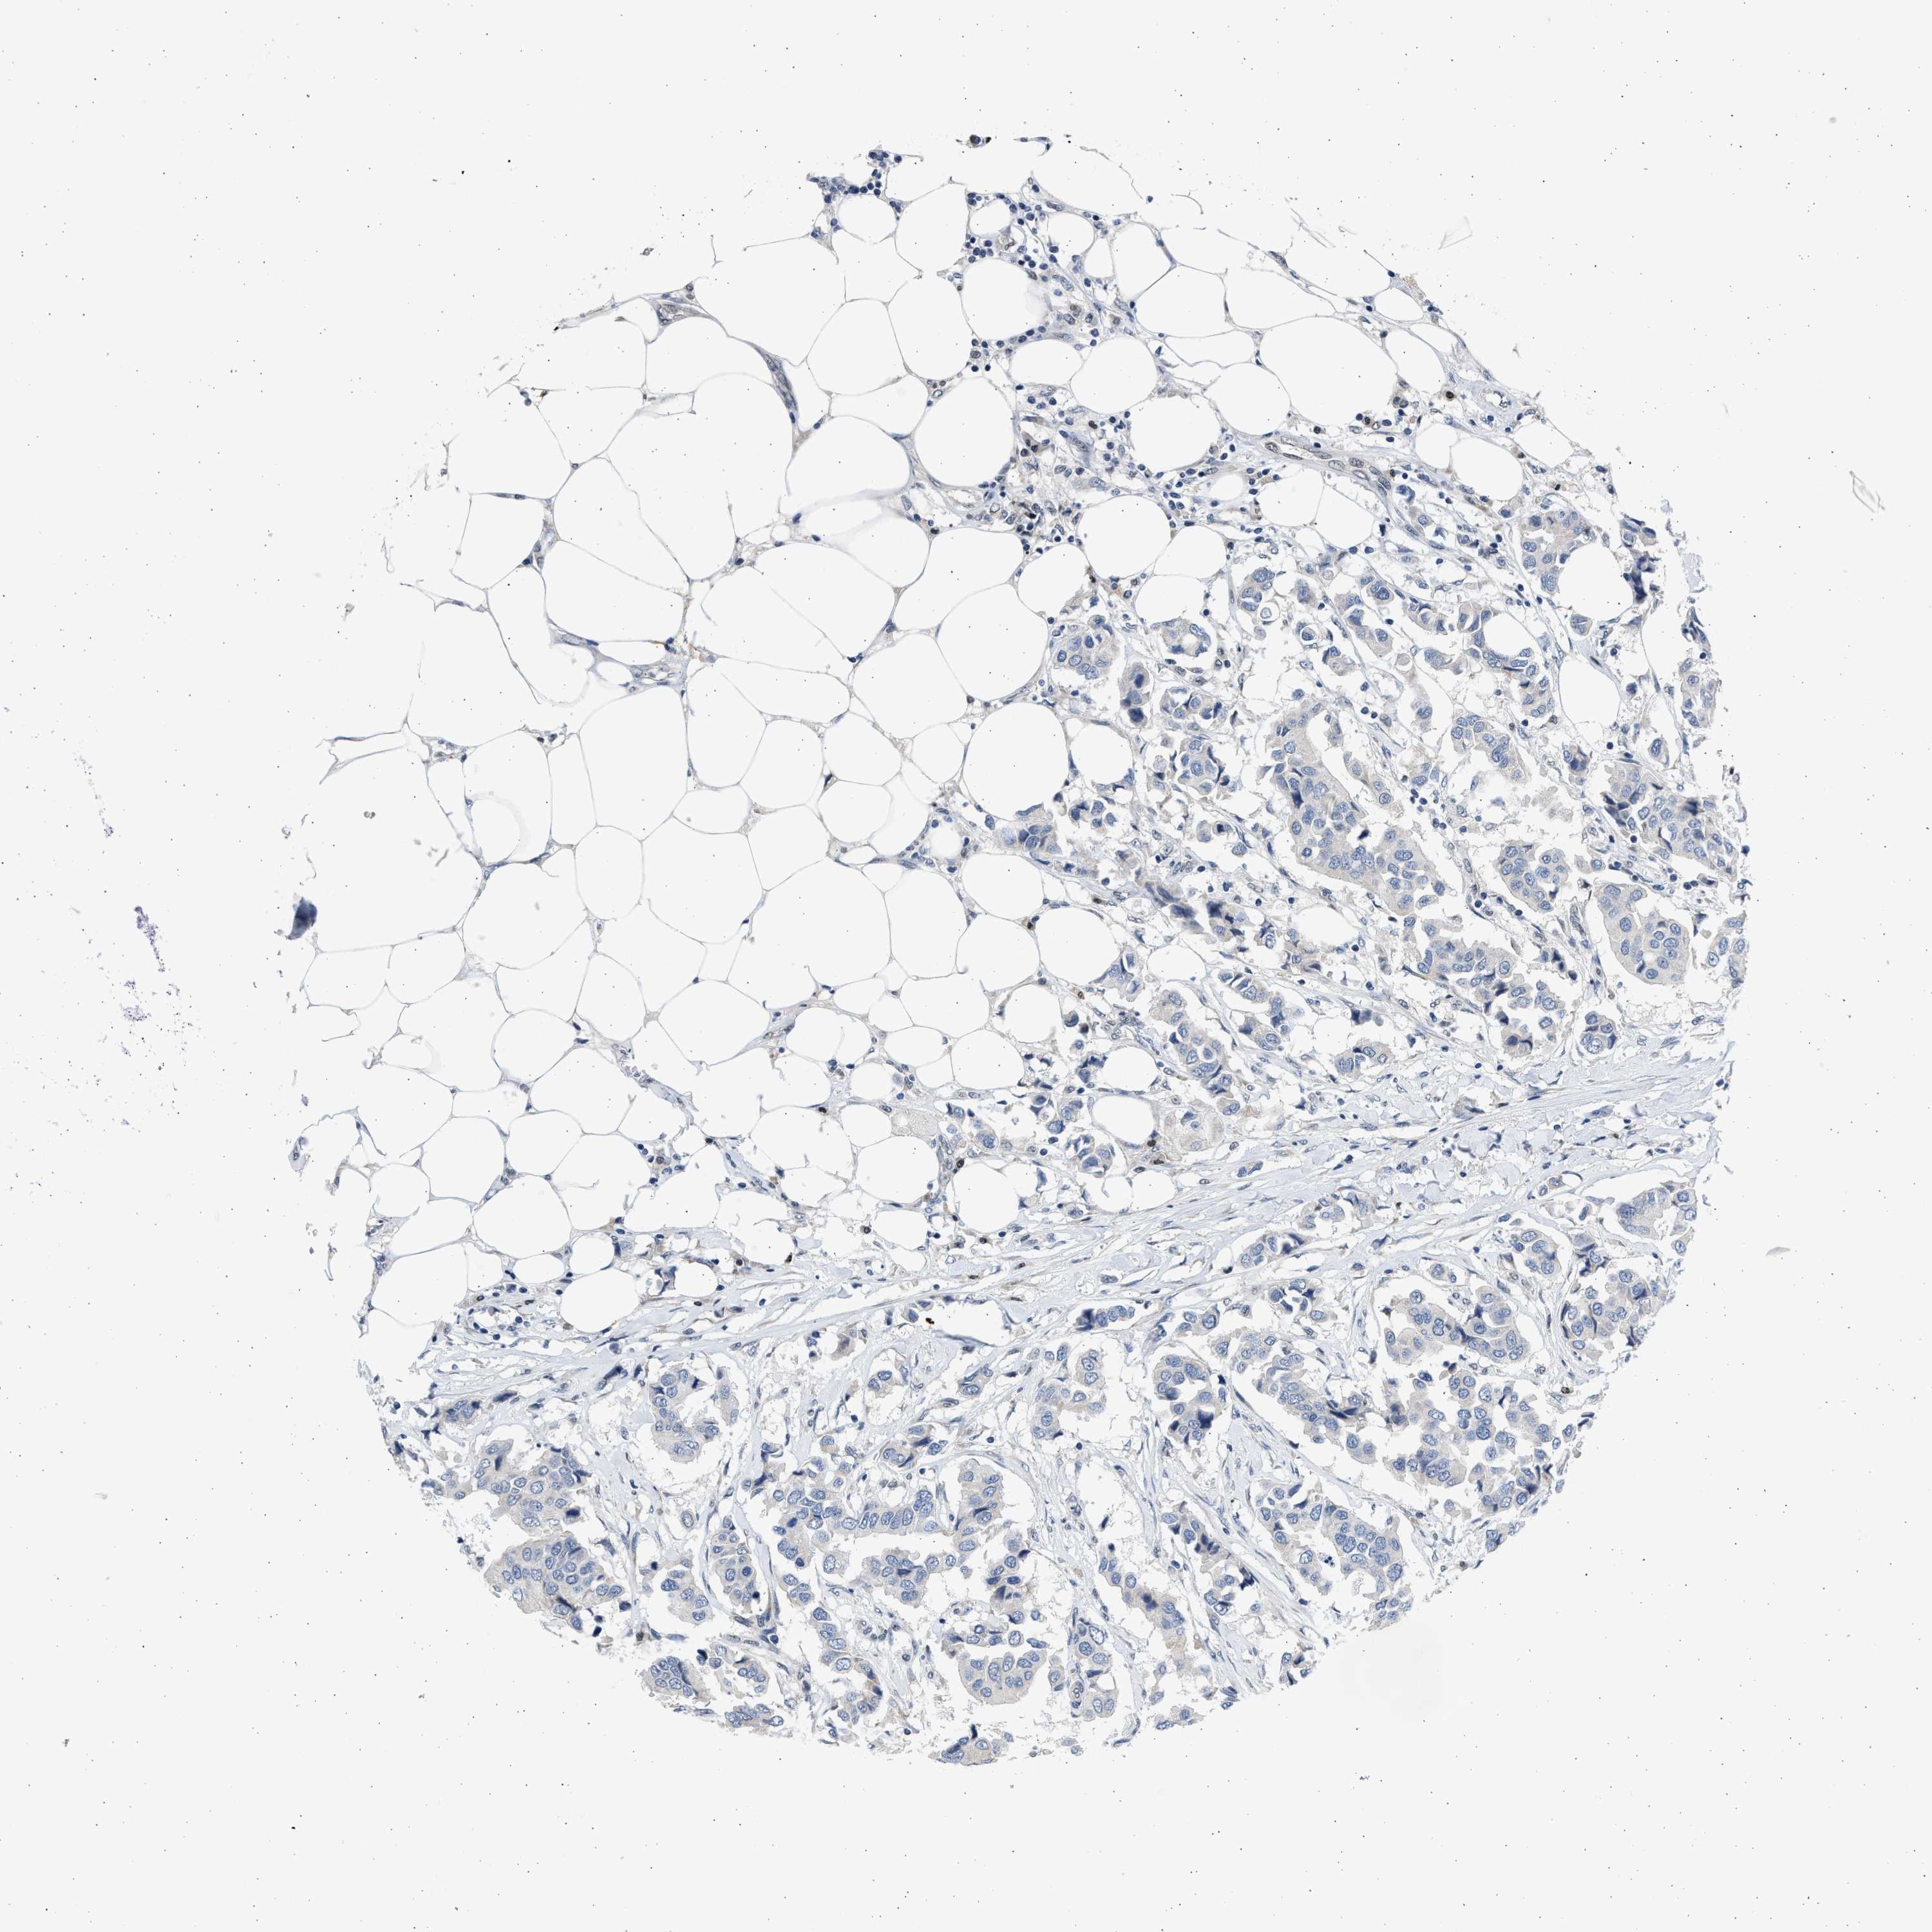

CANCER BREAST CANCER Show tissue menu

BRCA TCGA BRCA VALIDATION PROTEIN EXPRESSION

ANTIBODIES

AND

VALIDATION